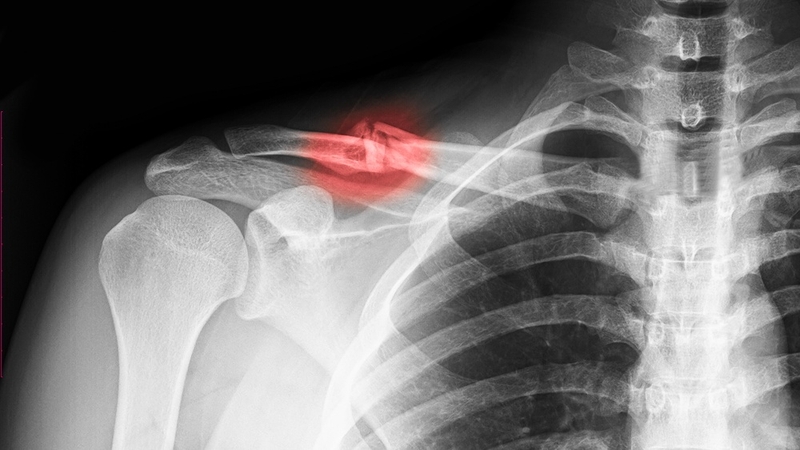

Gãy xương đòn là tình trạng phổ biến, có thể xuất hiện ở bất cứ độ tuổi nào. Bệnh lý này chiếm đến 5% trong tổng số các trường hợp gãy xương ở người lớn. Nguyên nhân chủ yếu bắt nguồn từ các chấn động mạnh như: Ngã do tai nạn giao thông, tai nạn khi tập luyện thể thao hoặc tai nạn lao động. Ở trẻ sơ sinh, xương đòn có thể bị gãy nếu mẹ sinh thường qua ngã âm đạo.

Thông thường, xương quai xanh thường bị gãy ở vị trí ⅓ của xương. Trong trường hợp nhẹ, xương có thể bị nứt hoặc lệch. Nếu nghiêm trọng hơn, xương sẽ gãy thành nhiều đoạn nhỏ. Do xương đòn nằm nổi ngay dưới cổ nên tất cả các dấu hiệu bất thường có thể được phát hiện dễ dàng bằng cách quan sát hoặc chạm, sờ vào.